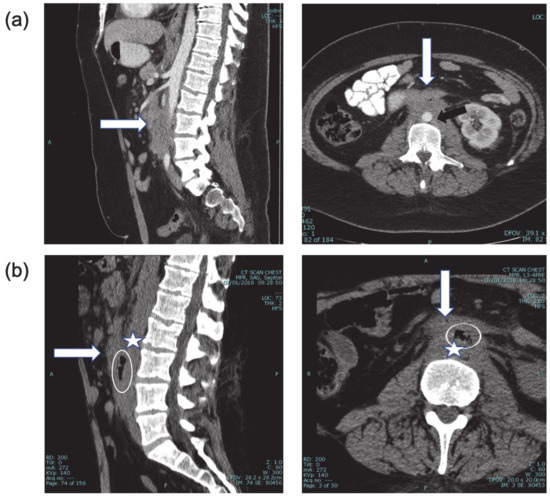

Figure 1. (a) CT + intravenous contrast, three months prior to bleeding event, showing the extent of disease (white arrow) around the abdominal aorta (black arrow) and relationship to duodenum (sagittal and axial views). (b) CT of the spine one month prior to bleeding. Sagittal and axial views. With retrospect, air (encircled) was identified between the aorta (star) and duodenum (arrow), highly suspicious for aorto-duodenal fistula.

A 29-year-old male patient suffering from Hodgkin’s lymphoma, which relapsed after multiple lines of therapy, including autologous bone marrow transplantation, pembrolizumab, and brentuximab vedotin, presented with rapid intra-abdominal progression (Figure 1), and received one course of ICE (Ifosphamide, Cis-platinum, Etoposide) and one course of GDP (Gemcitabine, Dexamethasone and Cis-platinum) chemotherapy protocols. One week following the last dose of therapy, he arrived at the Hematology Day Care because of severe weakness, with hemoglobin of 5.7 gr%, but no signs of active bleeding. After receiving three units of packed red blood cells (PRBC) he was discharged home in a stable condition. The day after discharge, he presented to the emergency department with hematemesis, rectal bleeding, and anemia of 7.0 gr%. After administration of two units of PRBC, an upper endoscopic evaluation was performed, demonstrating a small superficial distal esophageal laceration considered to be the source of the hemorrhage, and managed by local adrenalin injection. Later that night, the patient developed massive hematochezia, necessitating a transfusion of an additional three units of PRBC, and was transferred to the ICU, where he remained in a stable condition for additional 24 h. A repeated upper endoscopy has demonstrated no evidence of active bleeding. However, a few hours after the procedure, he again developed massive rectal bleeding, this time with severe hemodynamic instability.

Certain disease and patient characteristics carry a high risk for the development of AEF. Among these are an encasement by tumor of the aorta and the GI tract, especially at the level of the duodenum due to anatomical proximity, older age, and pre-existing aortic disease, such as aortic aneurysm. Identification of high-risk patients at the time of diagnosis might necessitate preventive intervention or modification of the treatment protocol. For example, if possible, a repair of pre-existing abdominal aneurysm should be considered prior to chemotherapy. Lymphomas in particular respond rapidly to the initiation of therapy, resulting in tissue gaps with increased risk of sepsis or bleeding. Of note, similar to our case, in previously reported cases of lymphoma-related AEF, bleeding was associated with treatment initiation [4,6]. Thus, we suggest a pre-phase of steroids or reducing the dose of chemotherapy in the first cycle, to allow for better tissue repair, and to reduce the chance of neutropenia or thrombocytopenia, in case of an emergent abdominal intervention. We also advise for the high-risk patients to be admitted during the first days of therapy, for close monitoring and rapid imaging studies as necessary.